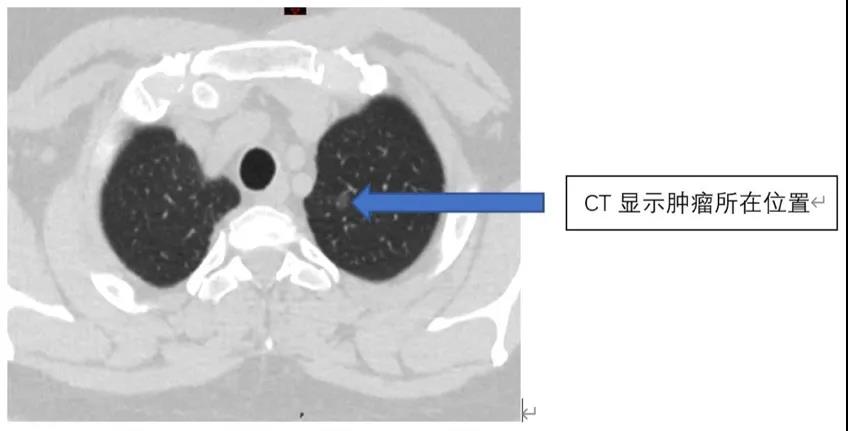

该名女性患者,约一年前体检时发现左肺上叶小结节。一年内多次 CT 复查提示左肺上叶结节有增大趋势,患者强烈希望通过手术方式进行治疗。

由于该患者的肿瘤发病属于早期,肿瘤直径小,在满足肿瘤根治原则的前提下,为了帮助患者更多地保留健康肺组织,实现快速康复,尽可能地提高术后长期生活质量,我科团队提出采用达芬奇机器人进行左肺上叶部分肺叶切除的外科方案,充分发挥智能微创精准外科的优势,让患者可以得到最大的手术获益。也得到了患者和家属的认可。